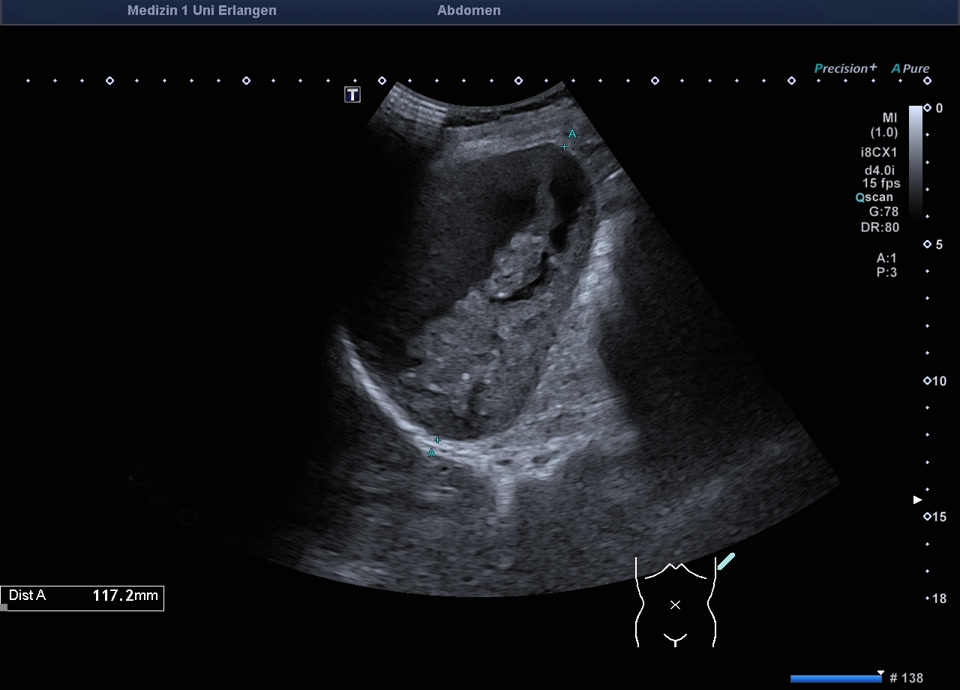

Kasuistik: 57-jährige Patientin mit einer Granulomatose mit Polyangiitis mit unklarer Leberwerterhöhung (ohne abdominelle Symptomatik). Im Ultraschall zeigt sich ein überraschender Milzbefund: Die Milz stellt sich großteils liquide dar, mit nur einem geringen Anteil soliden Gewebes, die Milzkapsel ist intakt. Die Kontrastmittelsonographie zeigt wenig erhaltenes und kontrastiertes Milzparenchym, ohne KM-Austritt in die flüssigen Anteile. Ein Trauma ist auf explizite Nachfrage nicht erinnerlich. Der Befund entspricht dem seltenen Fall einer asymptomatischen subtotalen Milznekrose, am ehesten im Rahmen einer nekrotisierenden Vaskulitis.